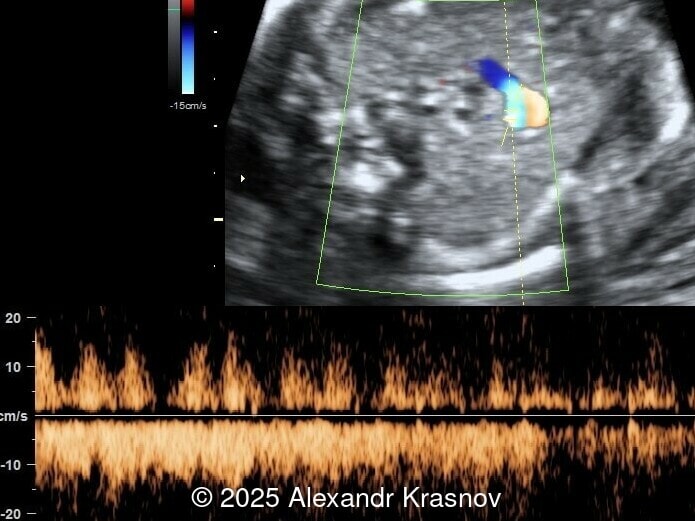

Image 3

Our ultrasound showed biometry data corresponding to 21 weeks of gestation. During echocardiography, an abnormal drainage of the pulmonary veins was detected in which the pulmonary veins drain into a venous collector linked to the superior vena cava. The four-chamber view and the three-vessel view were altered and raised suspicion of a pathology. The grayscale and color Doppler images of the four-chamber view indicate a smooth posterior wall of the left atrium, increased distance between the left atrium and the descending aorta and the absence of pulmonary veins entering the left atrium (Image 1, 2; Video 1, 2). In the three-vessel view, the diameter of the superior vena cava appears larger than that of the aorta (Image 3, Video 3). In the images of the venae cava, a significant difference is seen between the diameters of the inferior and superior vena cava with significant enlargement of the superior vena cava (Image 4, Video 4). Additionally, there is a pulmonary venous confluent chamber (“twig sign”) behind the left atrium (Image and Video 5). A vertical ascending vein connects the confluent chamber with the superior vena cava where it drains blood from the pulmonary veins (Images 6, 7; Video 6).

In many cases, direct signs are not visualized, thus identification of indirect signs allow us to suspect this pathology, not diagnose it. They are based on morphological findings such as increased post‑left atrium space, or on hemodynamic changes such as ventricular disproportion, dilated superior vena cava or coronary sinus, and abnormal Doppler waveforms. The presence of a pulmonary venous confluence leads to an increased distance between the left atrium (LA) and the descending aorta (DAo) [9]. While visualization of the confluent chamber may be difficult, objectively measuring the increase in the space behind the left atrium in an axial section may be easier to verify. Various indices have been proposed for this purpose, the most widely used being the “post‑LA space index” described by Kawazu et al [10]. It is calculated as the ratio of the LA‑DAo distance to the diameter of the DAo, proposing a value ≥1.27 as a potential marker of TAPVR. In clinical practice, a cut-off of 1.0 may be more useful to increase detection rates, although this would be at the expense of more false positives. An alternative marker with a similar diagnostic performance and independent of the gestational age is the “left atrial posterior space to diagonal ratio,” which is calculated by dividing the LA‑DAo distance by the left atrial diameter, with an optimal cut-off ≥0.35 [11]. Asymmetric ventricular chamber dimensions with right heart dominance result from extra‑abnormal flow from the pulmonary veins to the right heart, providing a diagnostic clue for TAPVR [9], but this finding is late and not very specific. In supracardiac TAPVR, anomalous pulmonary venous drainage increases blood flow to the collector, which travels to the right atrium through the dilated innominate vein and superior vena cava, visible in the three-vessel trachea and bicaval views [7,12]. In the subcostal view of pediatric echocardiography, the cardiac type is characterized by the “whale’s tail sign,” where left and right pulmonary veins drain into the dilated coronary sinus. Although it is a technically difficult plane to obtain in fetal echocardiography, it has been described by Karmegaraj in a 25-week-old fetus [13]. Spectral Doppler waveforms are typically normal or biphasic in cardiac type, whereas in supracardiac and infracardiac types, the waveforms can be biphasic, monophasic, or continuous [6,7]. Color and spectral Doppler assessment allows the identification of the fetuses with pulmonary venous pathway obstruction and, therefore, at risk for acute postnatal deterioration with severe respiratory distress and cyanosis [14].